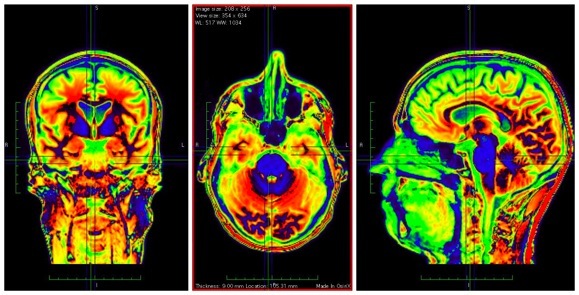

plan coronal

ou frontal

plan horizontal

plan sagittal

plan coronal

ou frontal

plan horizontal

plan sagittal